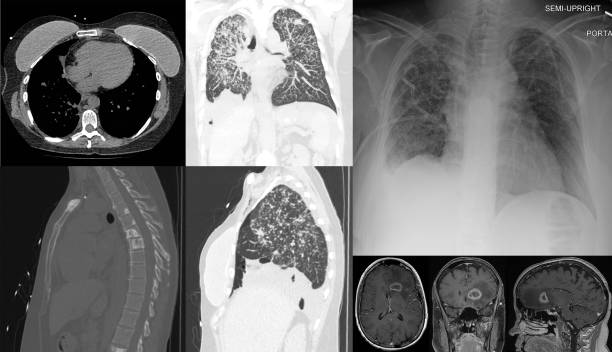

기흉이 의심되는 환자에게는 흉부 X선 검사를 실시하여 기흉이 있는지 확인할 수 있습니다. 이 방법은 비교적 쉽고 빠르게 기흉을 진단할 수 있습니다.

초음파 검사는 X선 검사와 비슷한 방법으로 사용됩니다. 이 방법은 폐 뿐만 아니라 심장, 간, 췌장 등 다른 장기도 검사할 수 있으며, 기흉의 정확한 위치를 파악할 수 있습니다.

CT 스캔 검사는 폐의 3D 영상을 생성하여 누출된 공기가 있는 위치와 기흉의 원인을 파악할 수 있습니다.